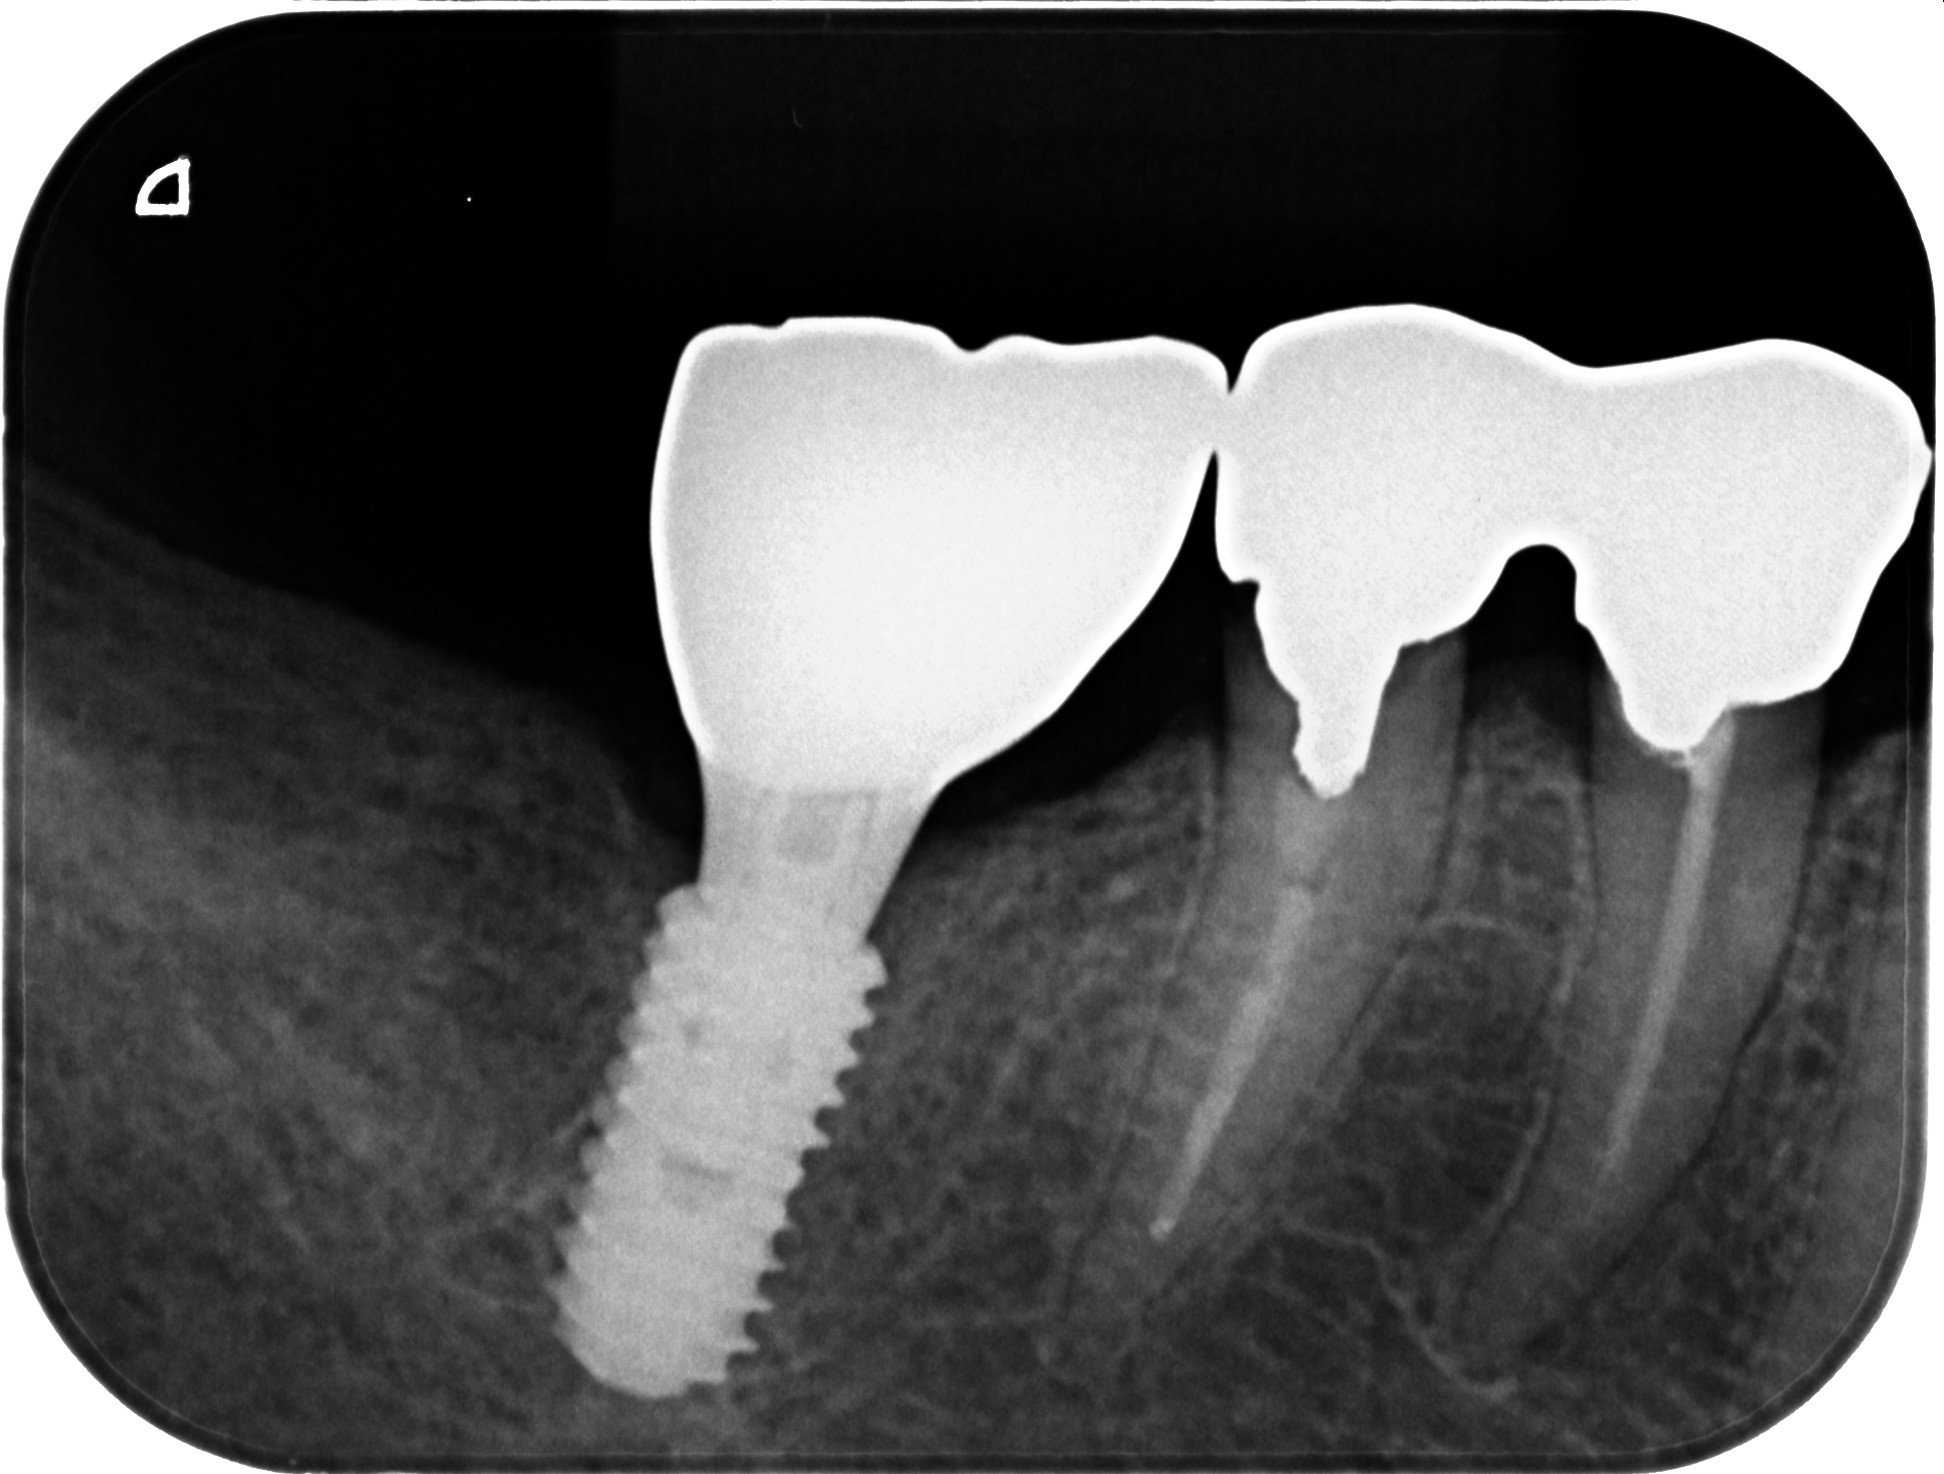

• インプラント

ソケットプリザベーション&インプラント症例|右下の奥歯が何もしなくても痛い

インプラント症例|右下の被せものがとれてしまった

右下インプラントブリッジ、左下インプラント症例

左下に歯の移植かインプラントか相談をしたい(インプラント症例)

入れ歯が使えなくて他の方法を考えている(インプラント症例)